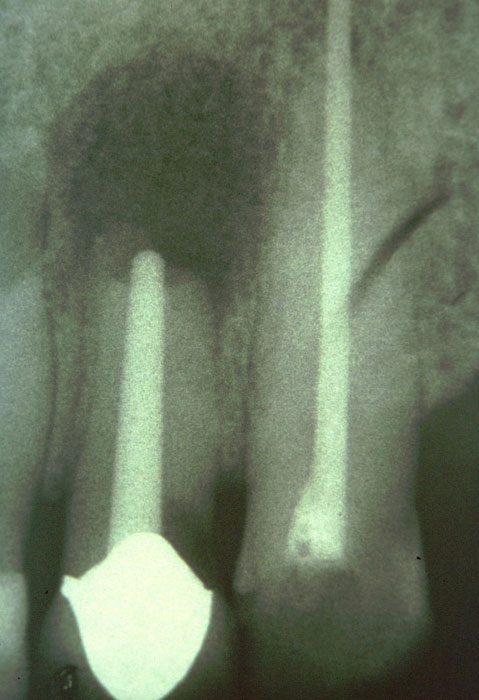

Oberer seitlicher Schneidezahn nach Wurzelspitzenresektion und Versuch der Reinigung und Obturation des vermeintlich runden und gerade verlaufenden Wurzelkanals durch Einsetzen eines groß dimensionierten Titanwurzelstifts

Extraktionsgrund: Chronische apikale Parodontitis

Die Vorbohrung und die Zement-Stiftkombination lassen in allen Bereichen

des Wurzelkanals große Anteile der Querschnittsausdehnung unbehandelt.

Über die approximal entstandene Sekundärkaries besteht außerdem eine

Migrationsmöglichkeit für Mikroorganismen in Richtung Neoapex.